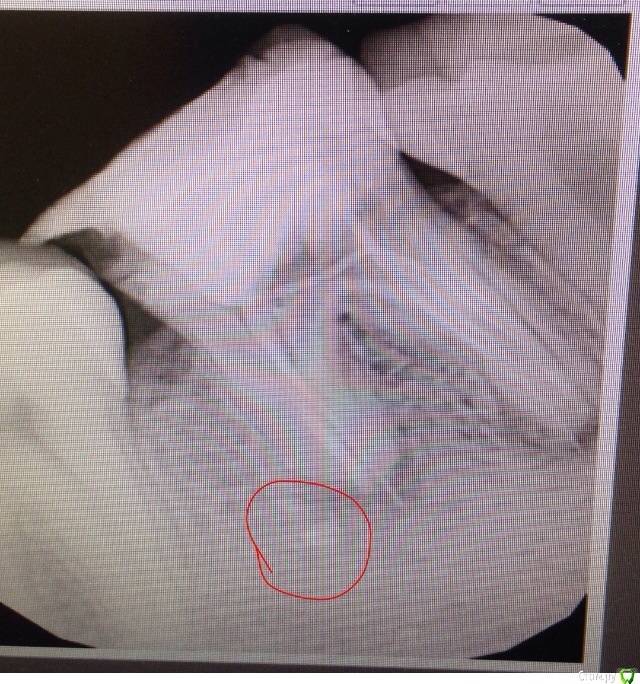

murlisa Опубликовано 3 апреля, 2017 Поделиться Опубликовано 3 апреля, 2017 может есть тут, те кто сталкивался с подобным, или даже стоматологи.Вобщем я лечу зуб, на котором стояла пломба еще давно- лет 7. Так вот после двух Гв кормлений, он начал буквально трещать по швам, весь потемнел, появились сколы, трещины. еще до второй беременности, когда я лечила все зубы, стоматолог поглядывала на него , и тогда предлагала поставить коронку, но я еле еле отошла от коронки на другой стороне нижней челюсти, и я сказала что повременим, и вот забеременела , откормила 2 года. И вот, взялась таки за него.Напримеме врач сделала снимок, (1фото)и сказала что у корня зуба, цитирую: "кальций", вскрыла, прочистила глубоко каналы, поставила пульпосептин, зуб после этого очень сильно болел и пульсировал пять дней, затем успокоился. Через две недели я пришла на повторный прием, и повторный снимок показал что ситуация ничуть не изменилась,(2 фото)и она поставила мне другое лекарство (не помню название). и вот сегодня я пришла на прием в третий раз. и опять та же картина(((( она развела руками, сказала что бессильна, отправила к другому врачу в другую клинику, дала мне их контакты. Добавила еще, что был похожий случай у одного мужчины, который после таких долгих мучений "психанул" и удалил его Ссылка на комментарий

murlisa Опубликовано 4 апреля, 2017 Автор Поделиться Опубликовано 4 апреля, 2017 с тем что Вы называете «кальцием», ничего делать не нужноспасибо. сегодня была на приеме, так и сказали, что это белое - ерунда, основная проблема на снимке оказалась в черном воспалении. его лечим. врач сказала что надежда спасти зуб все еще есть.... но лечение будет долгим и мучительным ....... Ссылка на комментарий